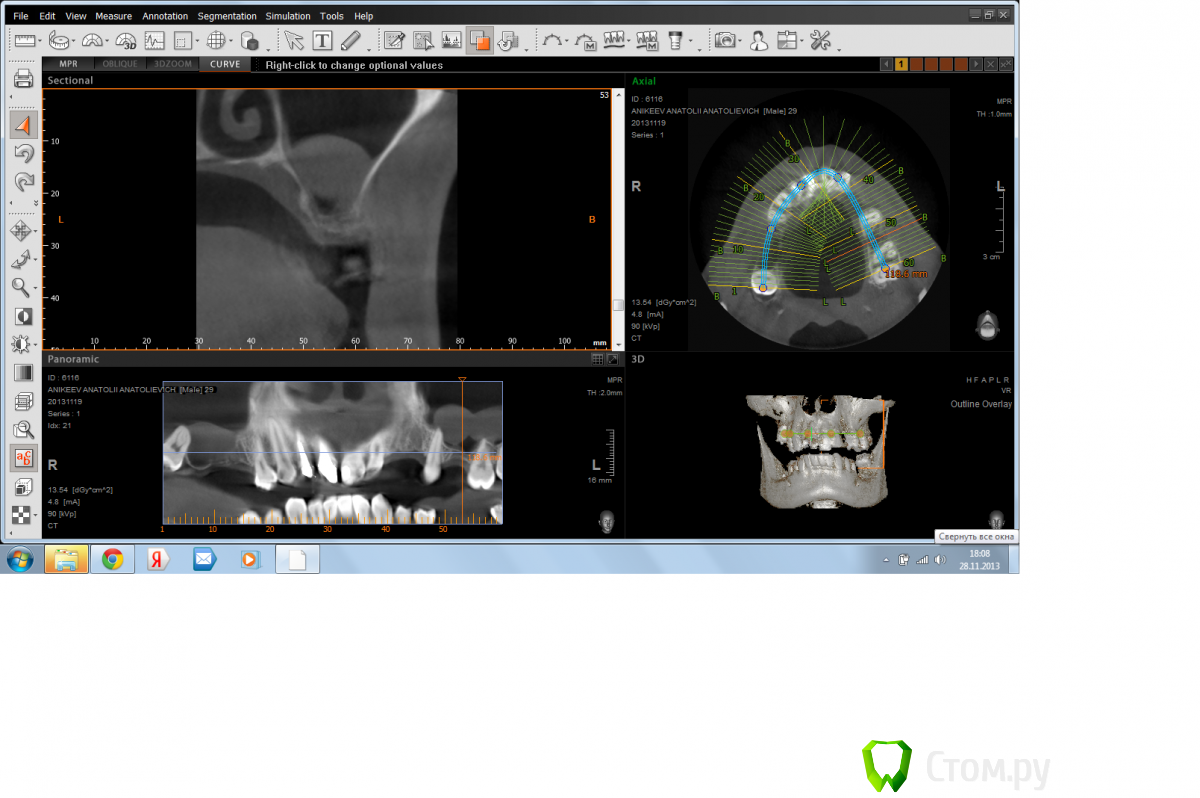

Doctorstomlis Опубликовано 29 ноября, 2013 Поделиться Опубликовано 29 ноября, 2013 Здравствуйте!У меня что-то подобное.Как Вы думаете,какова здесь тактика(я имею ввиду патологию в гайморовой пазухе) Ссылка на комментарий

ВИТА Опубликовано 31 января, 2014 Поделиться Опубликовано 31 января, 2014 Здравствуйте!У меня что-то подобное.Как Вы думаете,какова здесь тактика(я имею ввиду патологию в гайморовой пазухе)я бы сделала откр синус лифт аккуратно....по видимому это гипертрофия слизистой, подниматься даже лучше будет из-за своей плотности Ссылка на комментарий

Елена777 Опубликовано 1 февраля, 2014 Поделиться Опубликовано 1 февраля, 2014 Если клиники нет, я бы делала открыт синус. Ссылка на комментарий